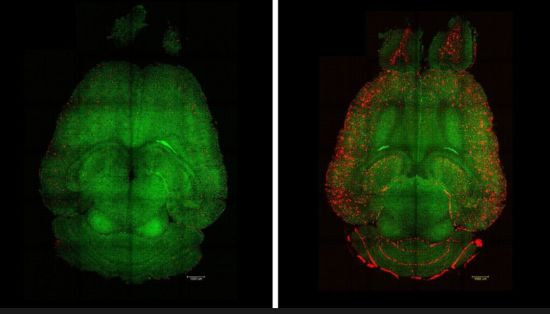

Así, en lugar de dirigirse directamente a las neuronas, la terapia restaura la función adecuada de la barrera hematoencefálica (BBB por sus siglas en inglés), el “guardián vascular” que regula el entorno del cerebro. Al reparar esta interfaz crítica, los investigadores lograron revertir la patología del Alzheimer en modelos animales.

El equipo de investigadores revelaron un mecanismo específico permite que las «proteínas de desecho» indeseadas producidas en el cerebro atraviesen la BBB, una barrera celular y fisiológica que separa el cerebro del flujo sanguíneo para protegerlo de peligros externos como patógenos o toxinas, y se eliminen en el flujo sanguíneo correctamente. En la enfermedad de Alzheimer, la principal proteína «de desecho» es la amiloide-β (Aβ), cuya acumulación perjudica el funcionamiento normal de las neuronas.

Los investigadores utilizaron modelos de ratón a los que administraron solo 3 dosis de los fármacos supramoleculares y posteriormente monitorearon regularmente la evolución de la enfermedad. Como destaca Junyang Chen, primer coautor del estudio, investigador del Hospital West China de la Universidad de Sichuan y estudiante de doctorado del University College London (UCL), «solo 1 hora después de la inyección observamos una reducción del 50-60% en la cantidad de Aβ dentro del cerebro».

«El efecto a largo plazo proviene de la restauración del sistema vascular del cerebro. Creemos que funciona como una cascada: cuando se acumulan especies tóxicas como la beta amiloide (Aβ), la enfermedad progresa. Pero una vez que la vascularización puede funcionar nuevamente, empieza a eliminar Aβ y otras moléculas dañinas, lo que permite que todo el sistema recupere su equilibrio. Lo más relevante es que nuestras nanopartículas actúan como un fármaco y parecen activar un mecanismo de retroalimentación que devuelve esta vía de eliminación a niveles normales». señala Junyang Chen.